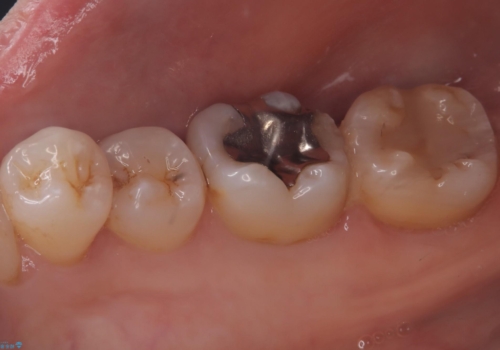

メタルインレーを歯冠色のものに変えたいという希望もあったため、セラミックインレーでのやり替えによるコンタクトの再現をしています。

また、近心側にう蝕が認められたため窩洞の範囲を元々入っていたメタルインレー窩洞よりも広げています。

セラミックインレーセット時ラバーダム防湿を行っています。